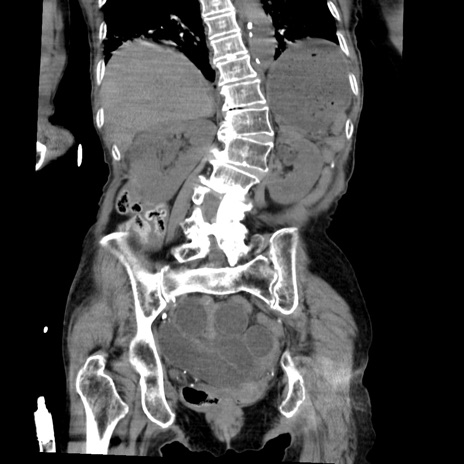

横断像

【症例】80歳代女性

【主訴】嘔吐、腹痛

【現病歴】数時間前より嘔吐あり。心窩部痛出現し、徐々に右下腹痛あり。その後も数回嘔吐あり救急搬送となる。

【既往歴】左大腿骨頚部骨折手術

【身体所見】腹部は膨隆しているが軟らかく圧痛なし。腸雑音はやや亢進。

【データ】WBC 12000、CRP 19.05